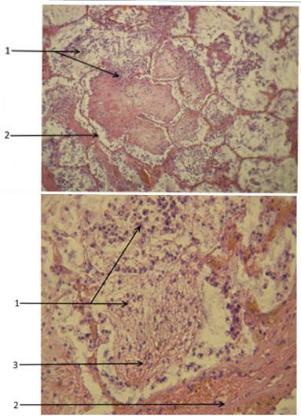

Карнификация Легкого: Микропрепараты и Диагностика

Раздел: Калейдоскоп образов